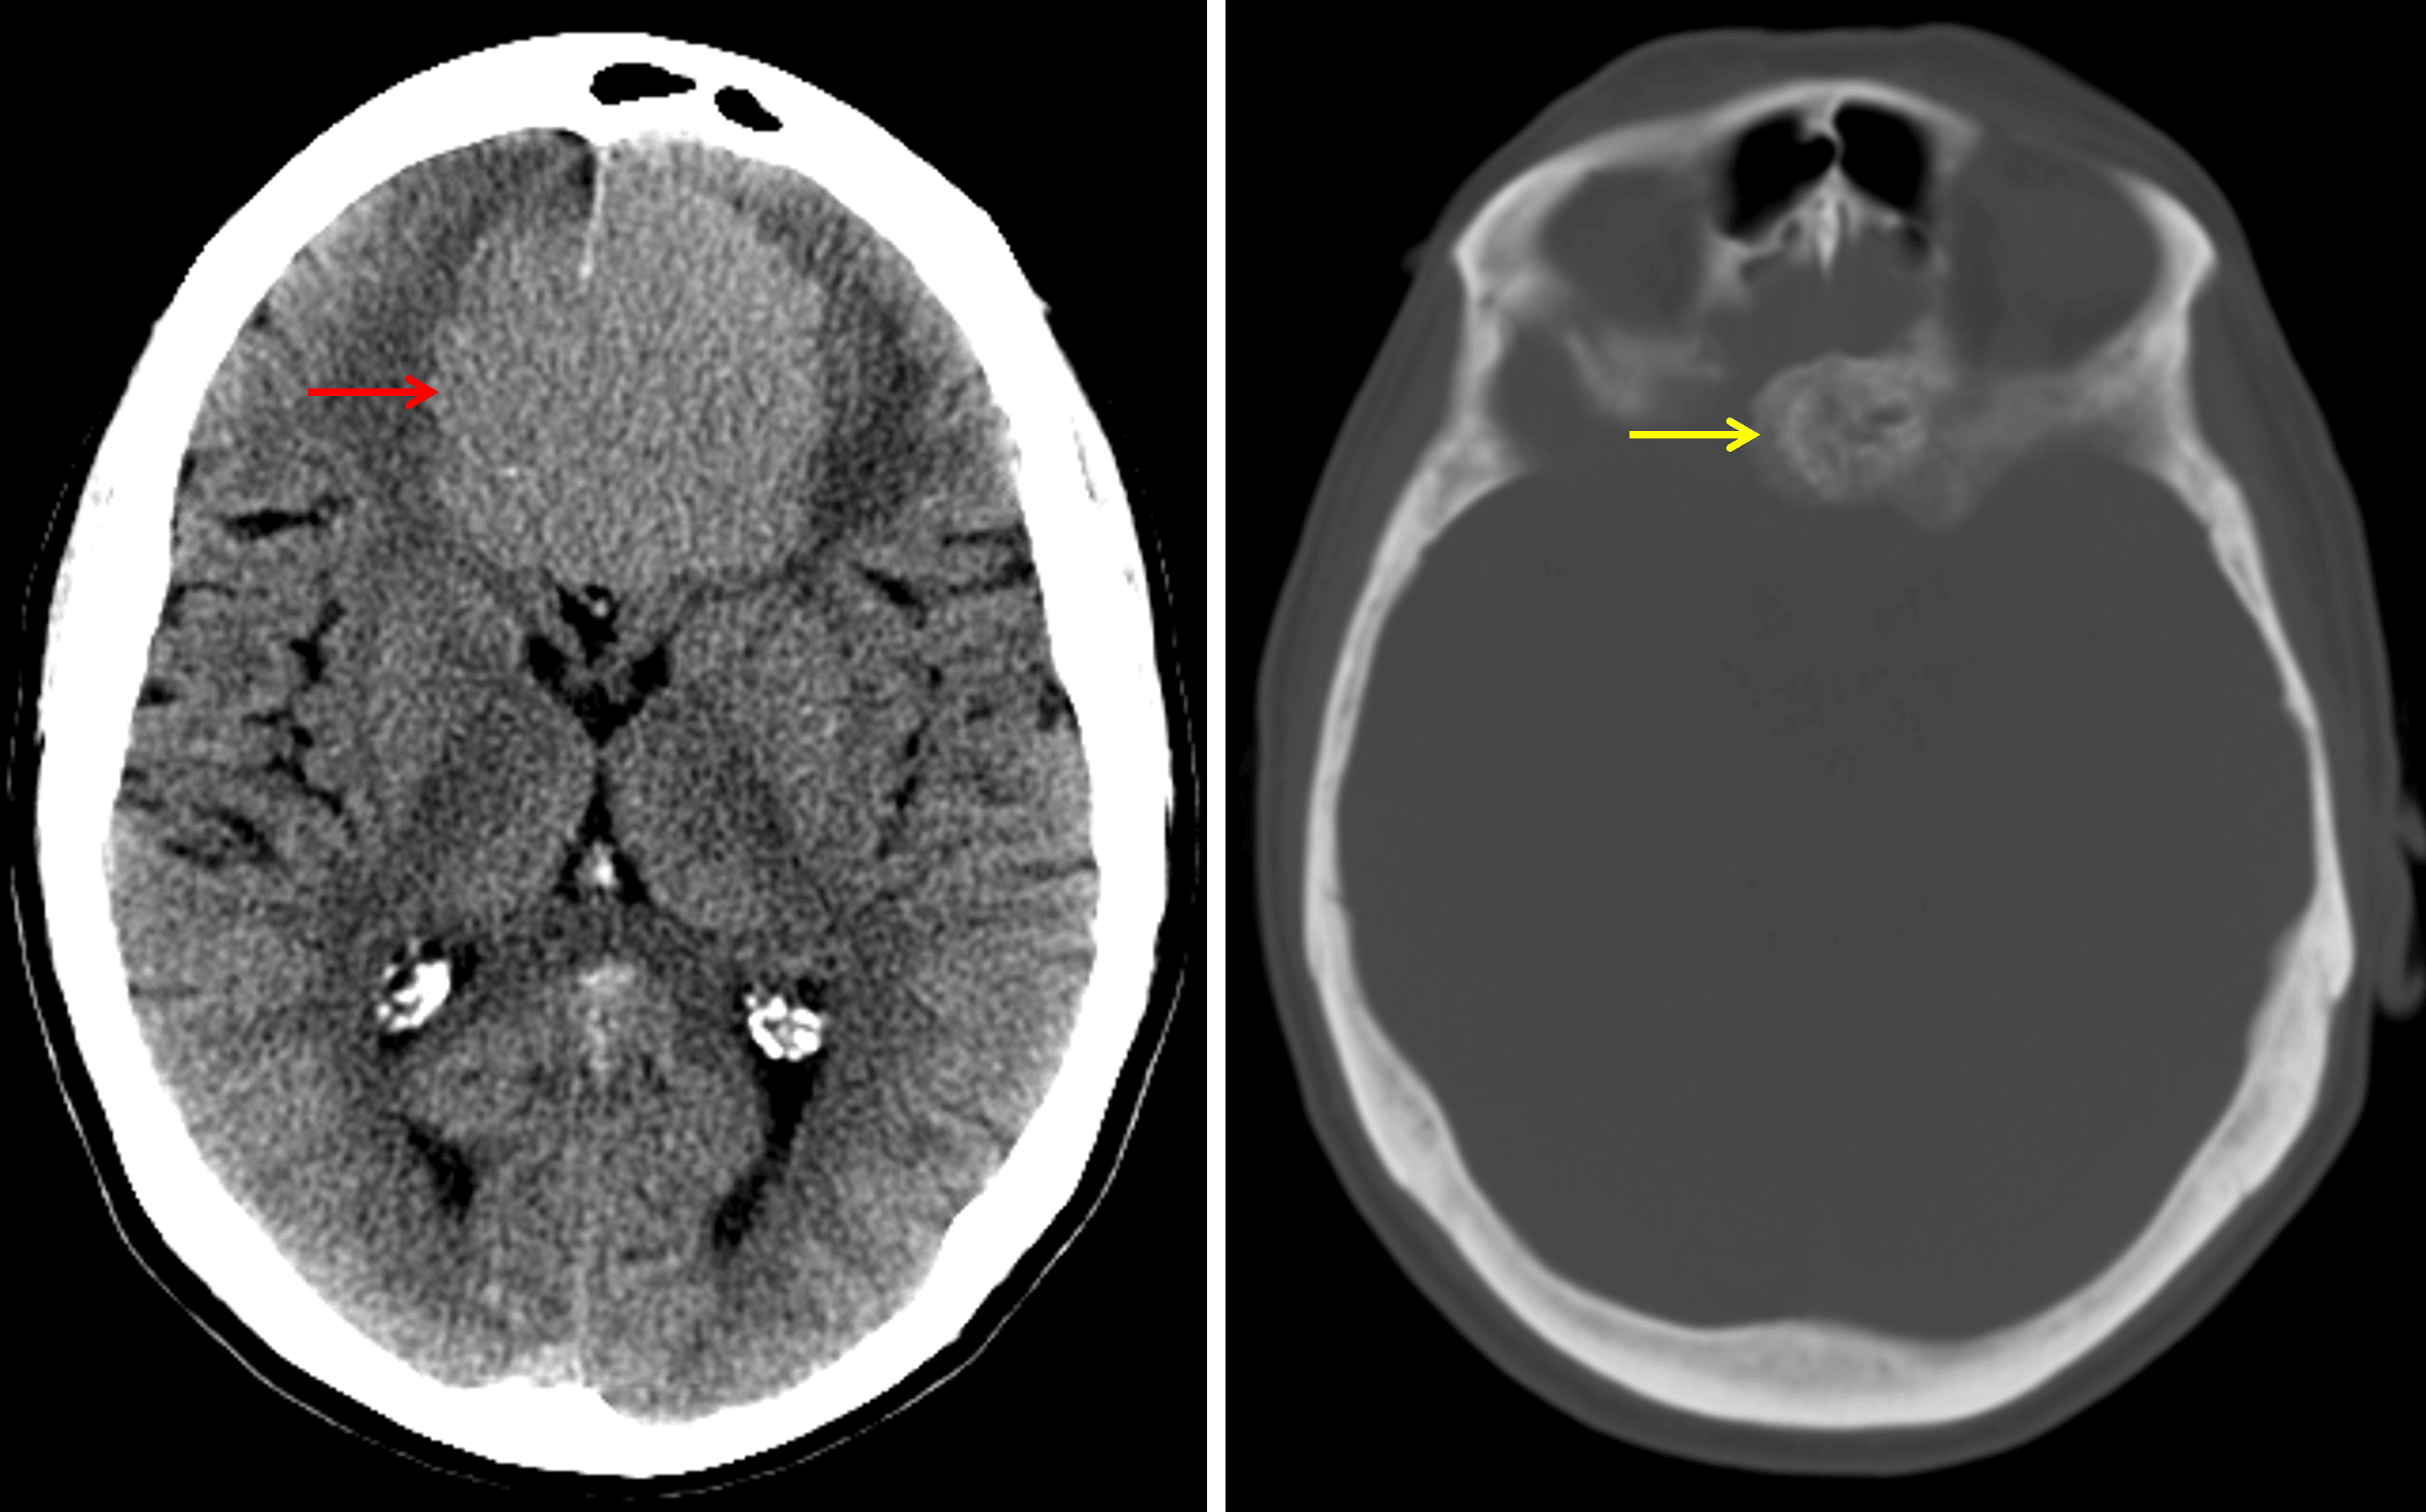

CT

- Large, mildly hyperattenuating extra-axial mass centered at midline in the anterior cranial fossa

- Corresponding calcification and adjacent hyperostosis along the olfactory groove

- Vasogenic edema in the adjacent left frontal lobe

- Associated mass effect on the frontal lobes, genu of the corpus callosum, and frontal horns of the lateral ventricles without herniation or hydrocephalus

Typical CT appearance of an olfactory groove meningioma, which is hyperattenuating relative to the brain parenchyma (red arrow) and demonstrates adjacent hyperostosis (yellow arrow).